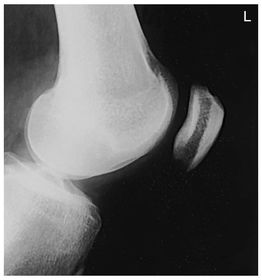

A. base of patella B. apex of patella C. tibial tuberosity D. neck of fibula E. head of fibula F. apex of head of fibula G. superimposed lateral and medial condyles H. patellar surface

Lateral Knee Mediolateral 40 SID 10x12 IR in table BUCKY - pt lateral recumbent w/ knee flexed 20-30 degrees so patella is perpendicular to IR - CR angled 5-7 degrees cephalic @ 1 in distal to medial epicondyle (Always angle for lateral) *seeing the adductor tubercle indicates the pt is underrotated* *seeing the distal borders of femoral condyles NOT superimposed indicates an incorrect cephalic CR angle*